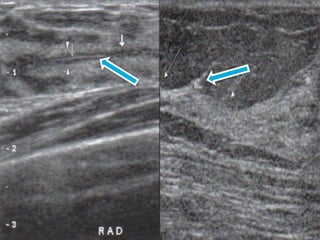

2.- ORIENTACIÓN RADIAL (ZONA

HORARIA)

 DOCUMENTAR DISTANCIA EN CM

 MENOS SUBJETIVO (MENOR VARIABILIDAD)

 3.-ORIENTACION DEL TRANSDUCTOR

 LONGITUDINAL, TRANSVERSAL, RADIAL

 RADIAL: VENTAJA EXPLORACIÓN EN

PARALELO AL EJE LONGITUDINAL DE LOS

CONDUCTOS